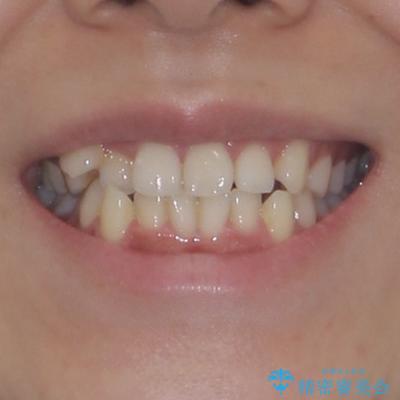

- 上下前歯のデコボコを気にして来院された患者様です。

上顎歯列が下顎の歯列に対して狭小であり、一部下顎の奥歯が上顎よりも外側に位置している状態でした。